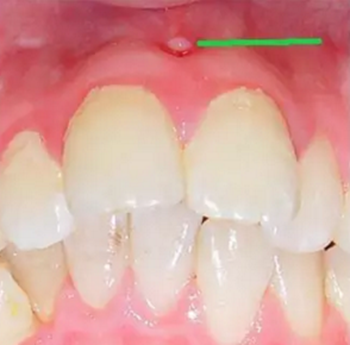

第一步:淺齲

當(dāng)我們身上有小黑點(diǎn)時(shí),您毫不在意地說(shuō):“沒(méi)事的,沒(méi)感覺(jué)。”

牙醫(yī)說(shuō):“齲病是由以細(xì)菌為主的多因素導(dǎo)致的牙齒硬組織發(fā)生慢性進(jìn)行性破壞的一種疾病。已經(jīng)開(kāi)始淺齲即牙釉質(zhì)齲,需要做藥物治療或充填治療。